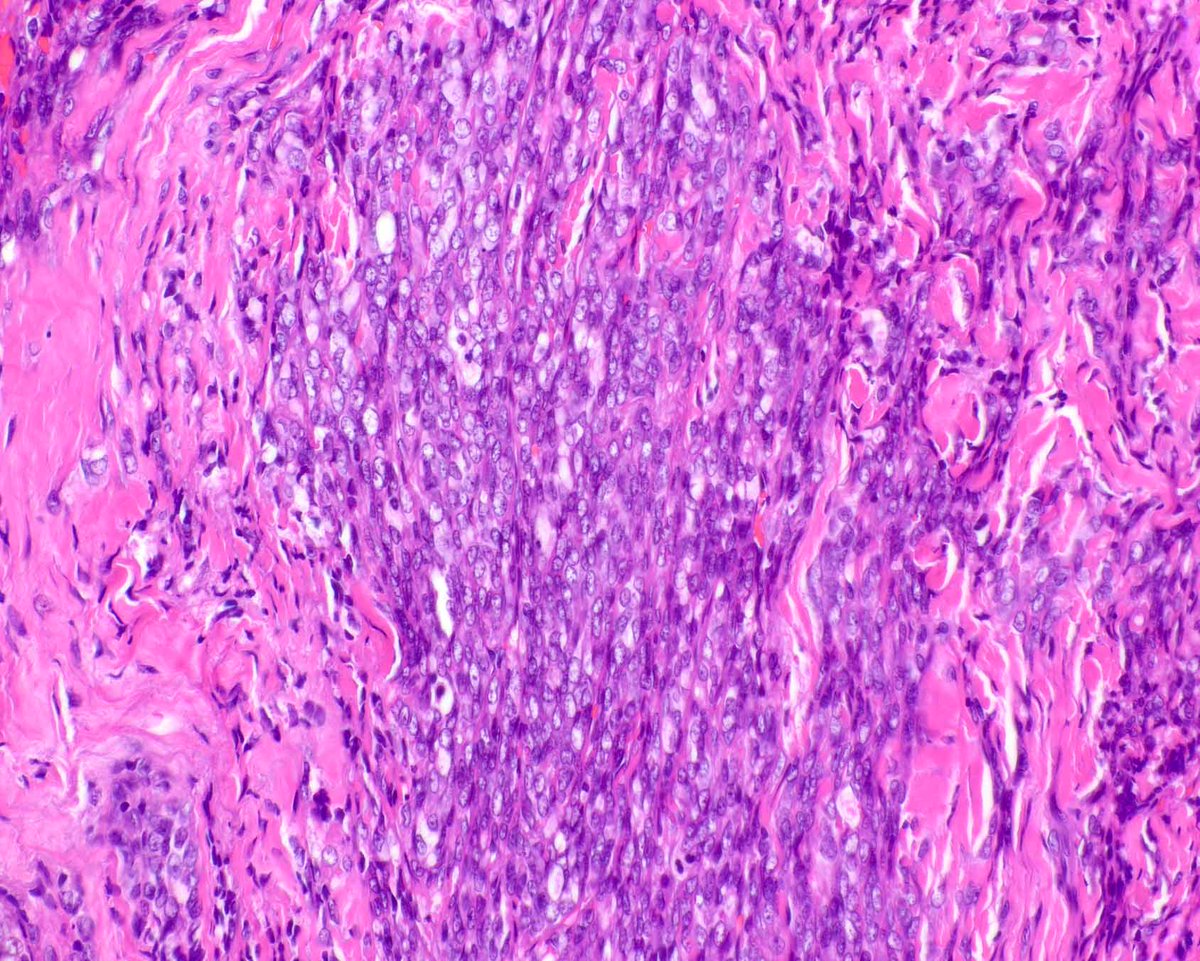

Proposed model for pathogenesis of malignant Brenner tumors of the ovary based on our study in @ModernPathology. Resemblance to #urothelial carcinogenesis and potential anti-FGFR3 targeted therapy implications (#erdafitinib). #OvarianCancer. Article link: rdcu.be/b8IFc